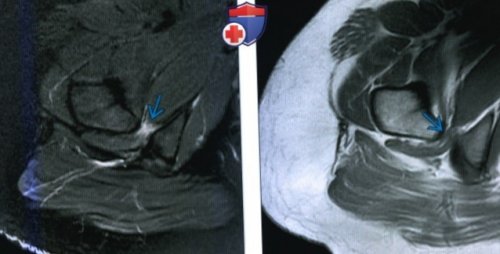

(Справа) МРТ Т2 ВИ, режим подавления сигнала

от жира, аксиальный срез: у этого же

о Отек или

вертела и седалищной • Т2ВИ:

о ± жировое замещение КМБ

и бугристостью седалищной о MPT: ↑ интенсивности сигнала на

— Оценка отека/жирового замещения мышцы